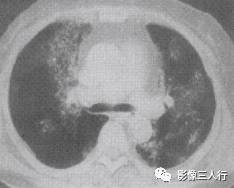

胸部CT图像显示,在含气少的致密肺的背景上见到含气的支气管,表现为两种形态: ①在大片肺实变病灶内的细条状空气密度影;②直径Imm的小泡状空气密度影,连续的几 个层面都能出现(图2、图3)。该征象表明:①近侧气道通畅;②肺泡内的空气经吸收(肺不张)或取代(肺炎、肺癌),或两者综合而消失。通畅含气的支气管在肺泡实变高 密度区内表现为管腔内低密度充气轮廓。